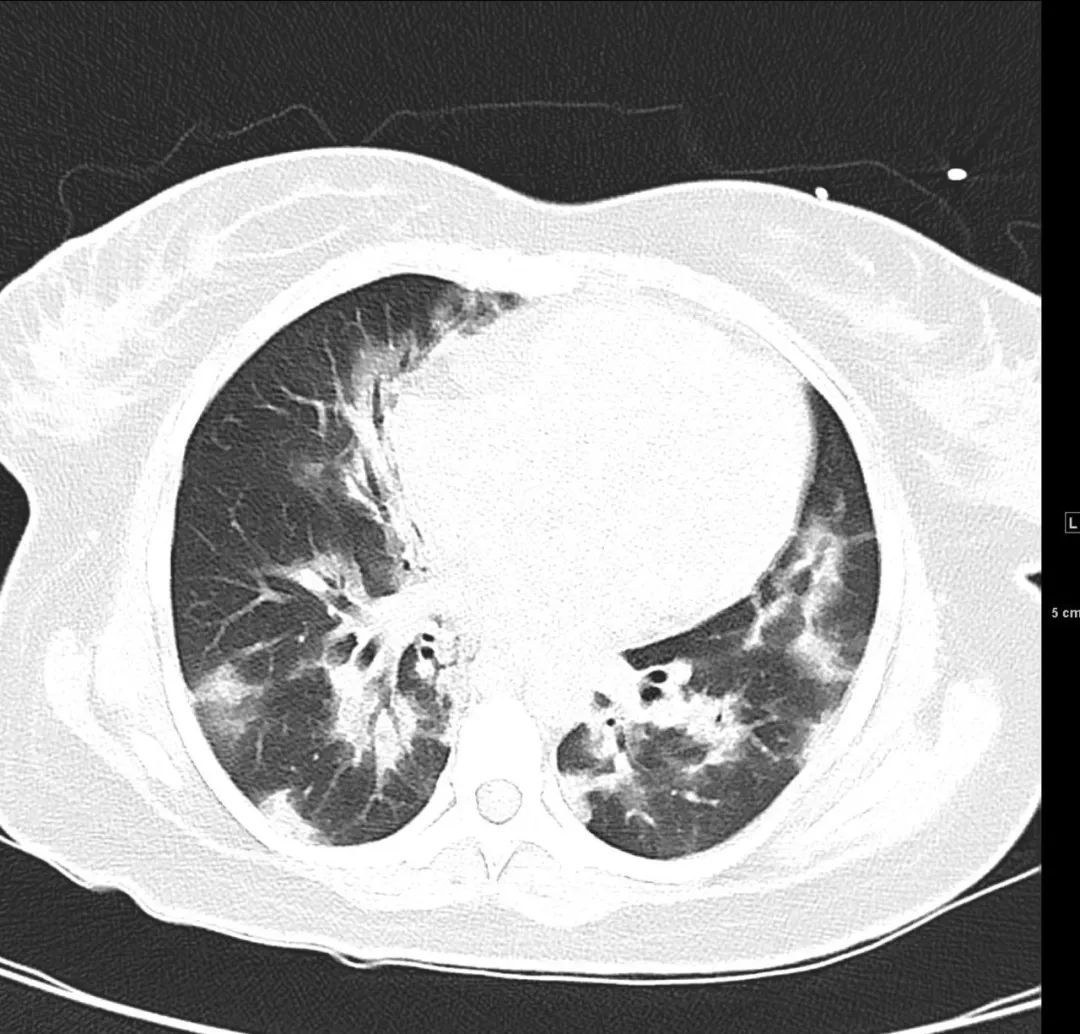

等等,我看到了最后面0.625mm序列的纵隔窗,我调成肺窗,和5mm厚层对准,终于找到了所谓磨玻璃结节的层面,原来是左肺叶间裂胸膜结节样增厚,在厚层上呈现结节。

这不是第一次将胸膜当成肺内结节,如果稍加注意,调一下窗宽窗位,可能就能避免使患者一家人惶惶不可终日,让他们多一些心安。

纵隔窗调成肺窗,显示左肺叶间裂结节样增厚